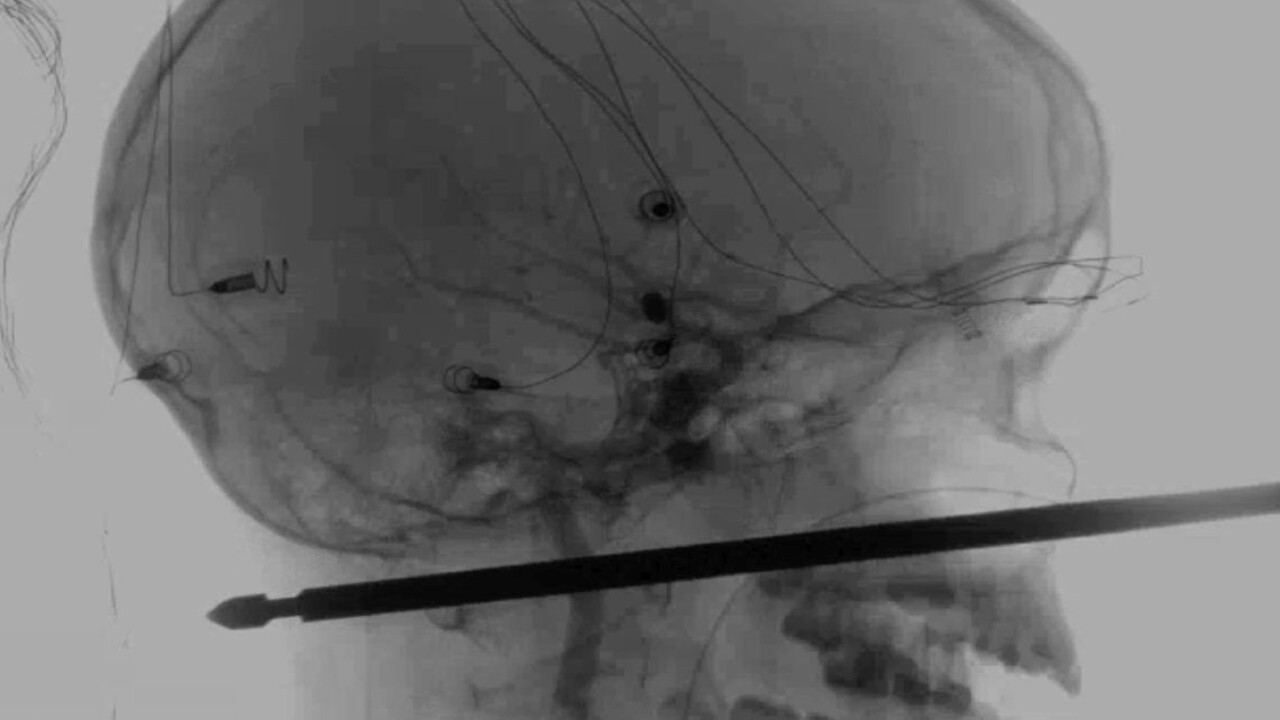

Desaťročný chlapec z amerického štátu Missouri sa zotavuje po tom, ako naňho zaútočil hmyz a zrútil sa zo stromu na zem, kde dopadol na kovový ražeň na mäso a ten mu prepichol lebku cez tvár až do zadnej časti hlavy.

Denník napísal, že lekári označili prežitie Xaviera Cunninghama za "zázrak". Xavierov hrozivý zážitok sa začal, keď naňho v domčeku na strome v rodinnej záhrade v meste Harrisonville zaútočili sršne. Chlapec spadol na zem, a keď jeho matka počula výkriky, rozbehla sa za ním. Lebku mal spredu dozadu prebodnutú polovicou 30-centimetrového kovového ražňa, ktorý mu stále trčal z tváre.

Šéf oddelenia neurochirurgie Lekárskej fakulty Univerzity v Kansase Koji Ebersole vyhlásil, že odstránenie ražňa v nedeľu nebolo jednoduché, ale ražeň minul Xavierovo oko, mozog, miechu aj hlavné cievy.